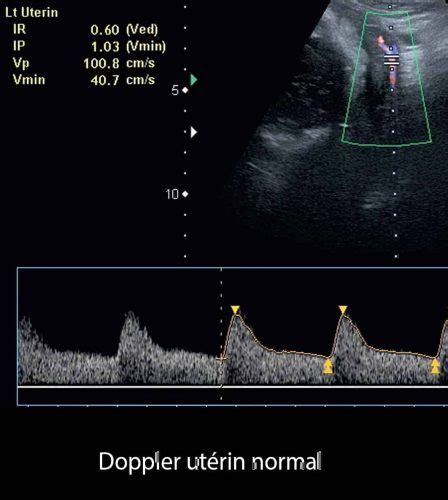

- Modificări ale circulației uterine, evidențiate ecografic prin Doppler.

- Evaluări Doppler:

- Fluxul în artera ombilicală: Rezistența la flux reflectă starea microvascularizației placentare.

- Fluxul în ductul venos (DV): Modificările apar în stadii avansate ale IUGR, indicând hipoxie și acidoză. Absența sau inversarea undei 'a' în DV este un predictor independent al riscului imediat de deces intrauterin în IUGR precoce.

- Fluxul în artera cerebrală medie (MCA): Scăderea rezistenței în teritoriul cerebral poate fi unicul semn Doppler în IUGR tardivă. Raportul cerebro-placentar (CPR), corelând pulsatilitatea MCA cu cea a arterei ombilicale, este util în diagnosticul IUGR tardive.